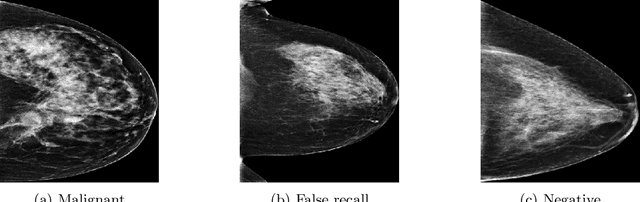

Abstract:Mammography is used as a standard screening procedure for the potential patients of breast cancer. Over the past decade, it has been shown that deep learning techniques have succeeded in reaching near-human performance in a number of tasks, and its application in mammography is one of the topics that medical researchers most concentrate on. In this work, we propose an end-to-end Curriculum Learning (CL) strategy in task space for classifying the three categories of Full-Field Digital Mammography (FFDM), namely Malignant, Negative, and False recall. Specifically, our method treats this three-class classification as a "harder" task in terms of CL, and create an "easier" sub-task of classifying False recall against the combined group of Negative and Malignant. We introduce a loss scheduler to dynamically weight the contribution of the losses from the two tasks throughout the entire training process. We conduct experiments on an FFDM datasets of 1,709 images using 5-fold cross validation. The results show that our curriculum learning strategy can boost the performance for classifying the three categories of FFDM compared to the baseline strategies for model training.